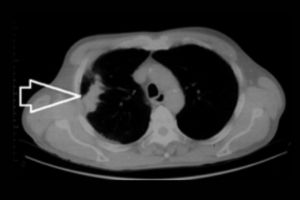

Are you looking for an affordable NCCT Right Leg scan? At Medifyhome, we offer competitively priced MRI and CT scans, partnering with top NABL-certified diagnostic centres and clinics. Our facilities ensure high-quality imaging and accurate results. An NCCT (non-contrast computed tomography) scan of the right leg is a diagnostic imaging procedure that provides detailed cross-sectional images of the bones and soft tissues of the leg without using contrast agents. This scan is commonly utilized to evaluate fractures, bone tumours, infections, and conditions affecting the vascular system. During the procedure, the patient lies still while the CT machine captures multiple images from different angles. The resulting high-resolution images help healthcare providers assess the integrity of the leg’s bones and surrounding tissues. The NCCT scan is quick, safe, and ideal for patients who may have allergies to contrast materials or need urgent evaluations. To book an appointment for an NCCT Right Leg scan, visit our platform, Medifyhome, or contact us at +919100907036 or +919100907622 for reasonable prices.

An NCCT (non-contrast computed tomography) scan of the right leg is a diagnostic imaging test that produces detailed cross-sectional images of the bones, soft tissues, and structures of the right leg without the use of contrast agents. This scan is used to evaluate various conditions, including fractures, bone tumours, infections, and vascular issues. It offers high-resolution images that help healthcare providers accurately diagnose and assess the extent of any problems affecting the leg. The procedure is quick and generally safe, making it suitable for patients who may be allergic to contrast materials or require immediate evaluation. Overall, the NCCT scan is a valuable tool in diagnosing and guiding treatment for leg-related issues.

- To identify and assess suspected fractures or stress injuries in the leg bones.

- To investigate the presence of bone tumours or abnormal growths in the leg.

- To detect infections such as osteomyelitis affecting the bones or soft tissues.

- To assess vascular issues, such as clots or other abnormalities in the blood vessels of the leg.

An NCCT scan of the right leg can detect fractures, tumors, infections, and vascular issues affecting the bones and soft tissues. It provides detailed images that assist in diagnosing various leg-related conditions and guiding treatment decisions.